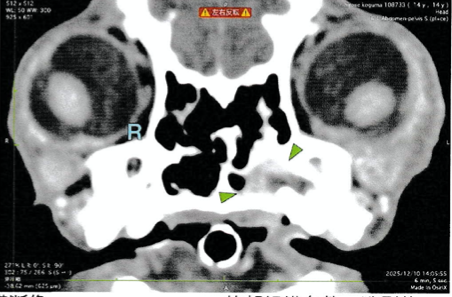

今回の症例は、くしゃみを主訴に来院されました。歯周病以外の疾患の除外と、歯周病箇所の場所の特定のため、CT検査を行いました。

左の上顎第1〜3前臼歯が鼻腔とつながっていることがわかったため、歯科処置にて、抜歯とフラップ形成を行いました。